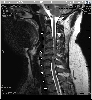

What all the fuss was about - my MRI. Notice that the spinal cord (the grey thing surrounded by white fluid) is pinched in two locations. Furthermore, there are white streaks in the spinal cord itself - that's it's way of going "ouch!", and those areas are damaged (myleopathy - literally, "death of nerves"). This is very bad, and if it continued, could have left me paralyzed.